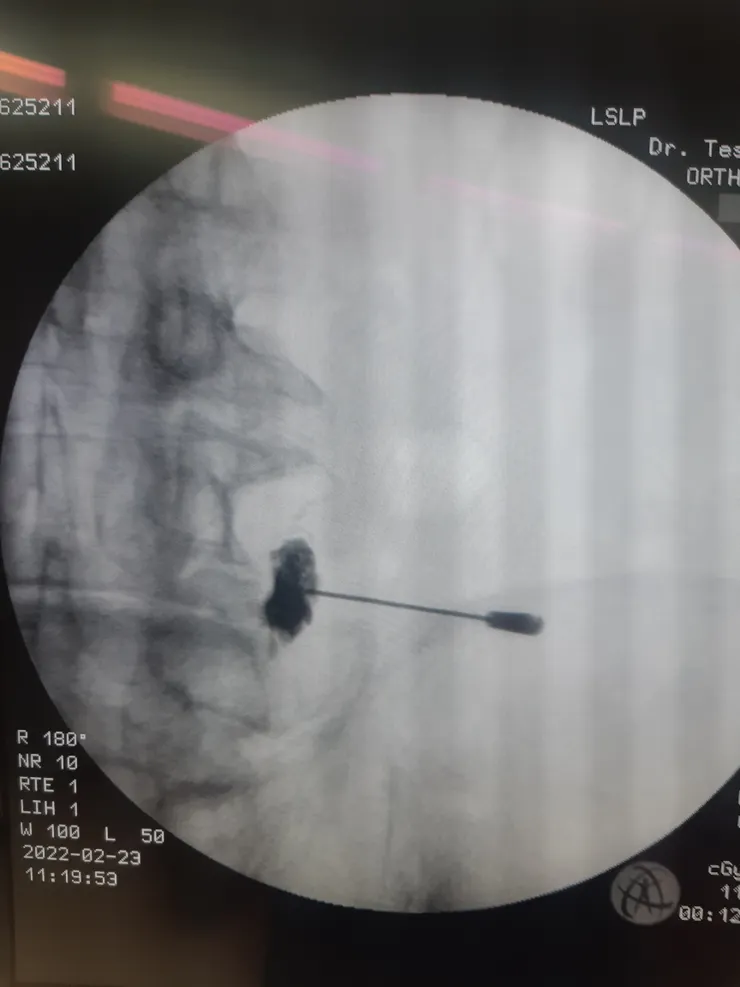

黑色團塊為顯影劑,為後續注射濃縮血小板血漿做標示